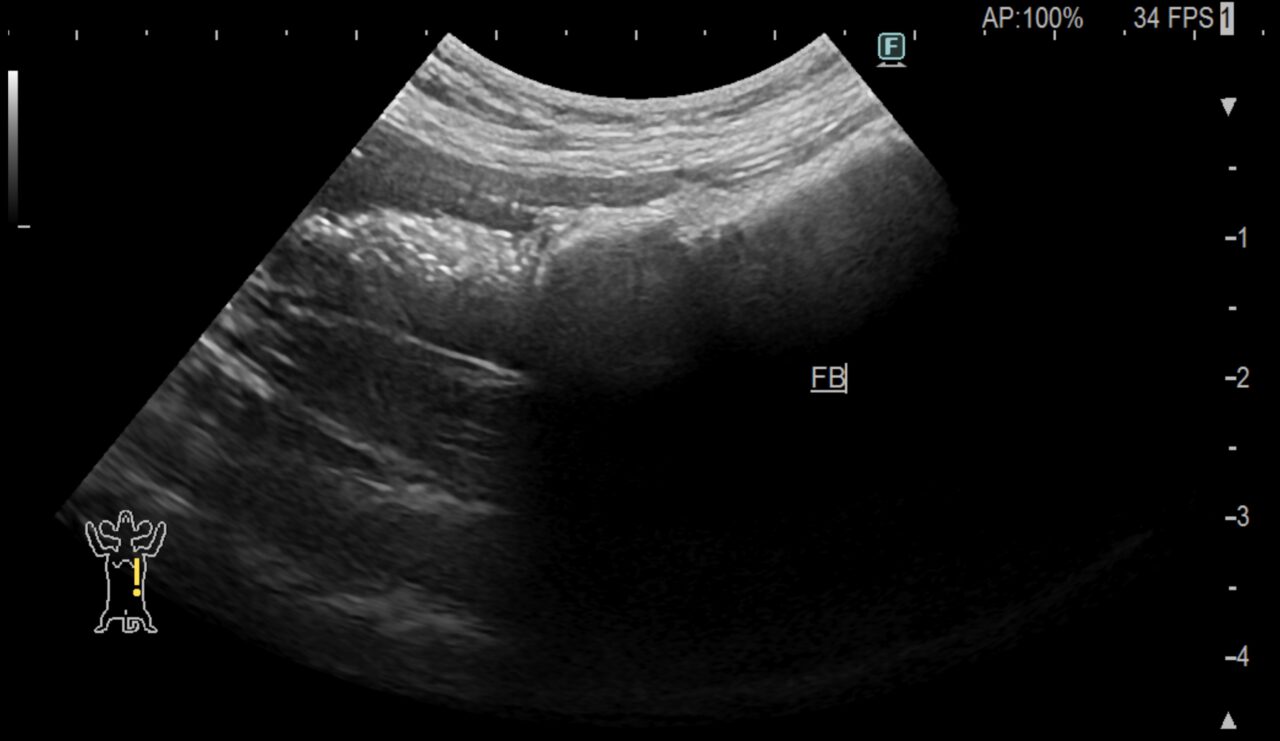

エコー検査を行うと小腸の空腸領域で異物が閉塞していることが確認できました。